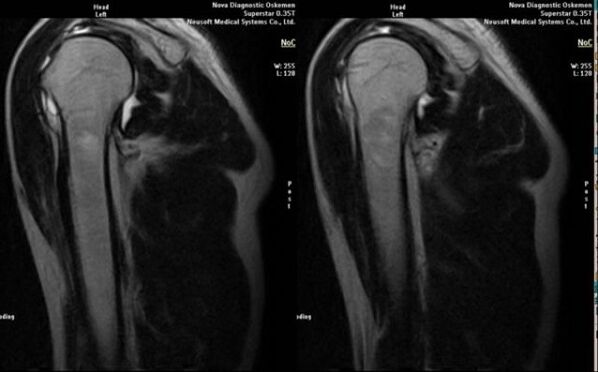

- магнитен резонанс и компютърна томография;

Признаците, показващи директно развитието на артроза, включват появата на значително стесняване на ставната цепка, склероза на подхрущялни структури, изтъняване на самия хондроцитен слой, поява на остеофити и отлагане на солни кристали във вътреставната течност.